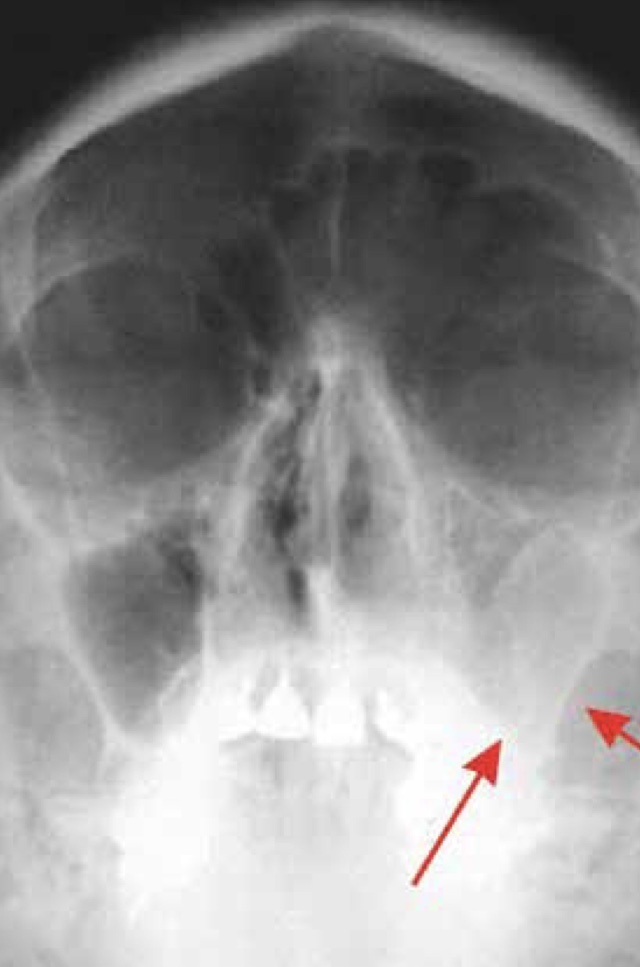

Achado e exame

Radiografia: velamento do seio maxilar esquerdo.